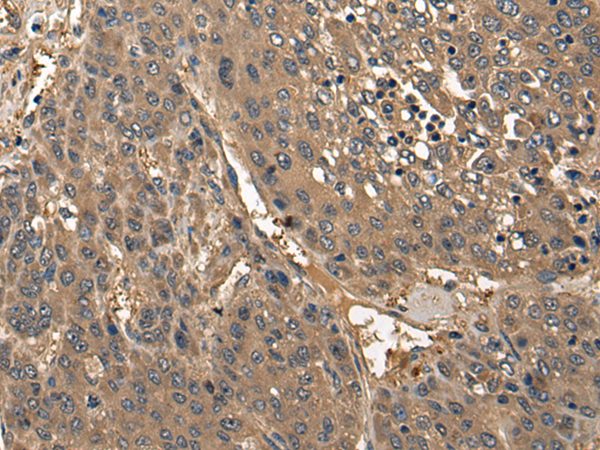

分类: 科研抗体货号: P06279别名:应用: WB,IHC反应种属: Human, Mouse, Rat